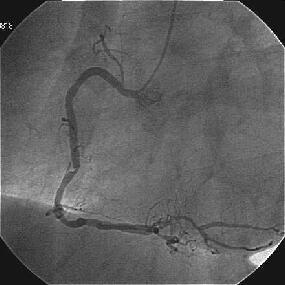

Crush�̎�Z�B

|

|

|

|